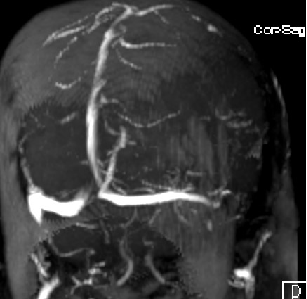

2015-1-30 DSA